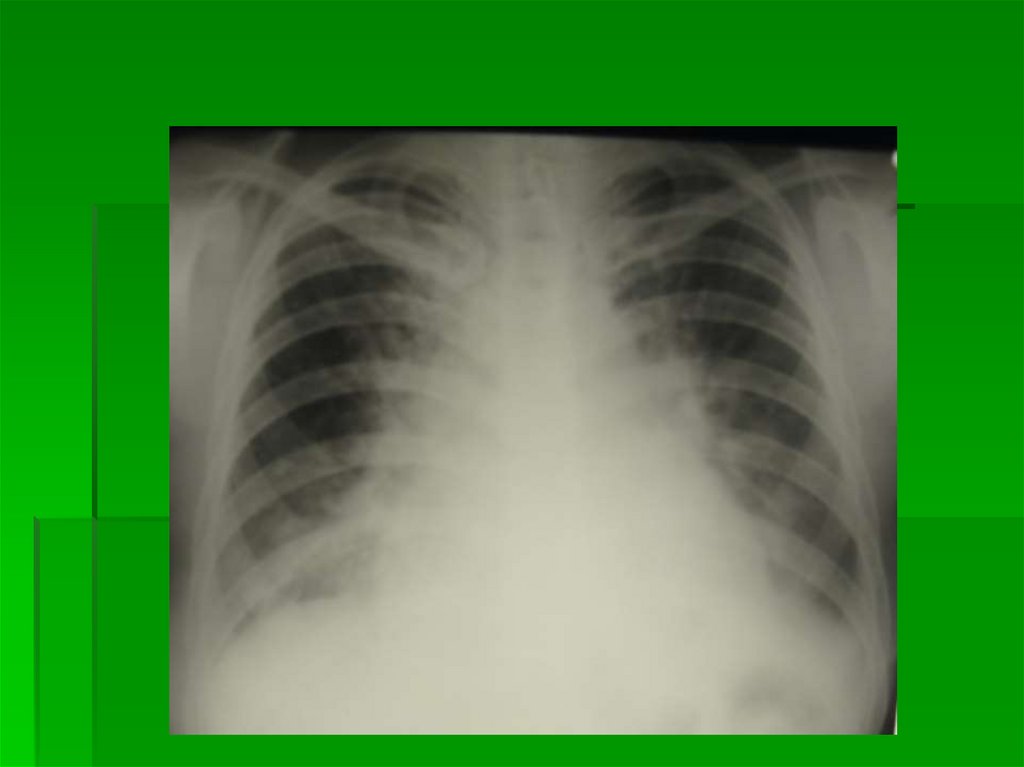

2 степень

Диффузный легочновенозный застой

P = 15-25 мм рт. ст

Симптомы перераспределения +

Корни неструктурны за счет проекционного наслоения

увеличенного количества сосудов в ортогональной

проекции

По всем легочным полям определяются расширенные

венозные стволы, их интенсивность и плотность

меньше интенсивности и плотности артериальных

стволов

Наружные контуры сосудов могут быть как четкие, так и

нечеткие (в зависимости от P в легочных венах)

2 степень Диффузный

легочно-венозный застой